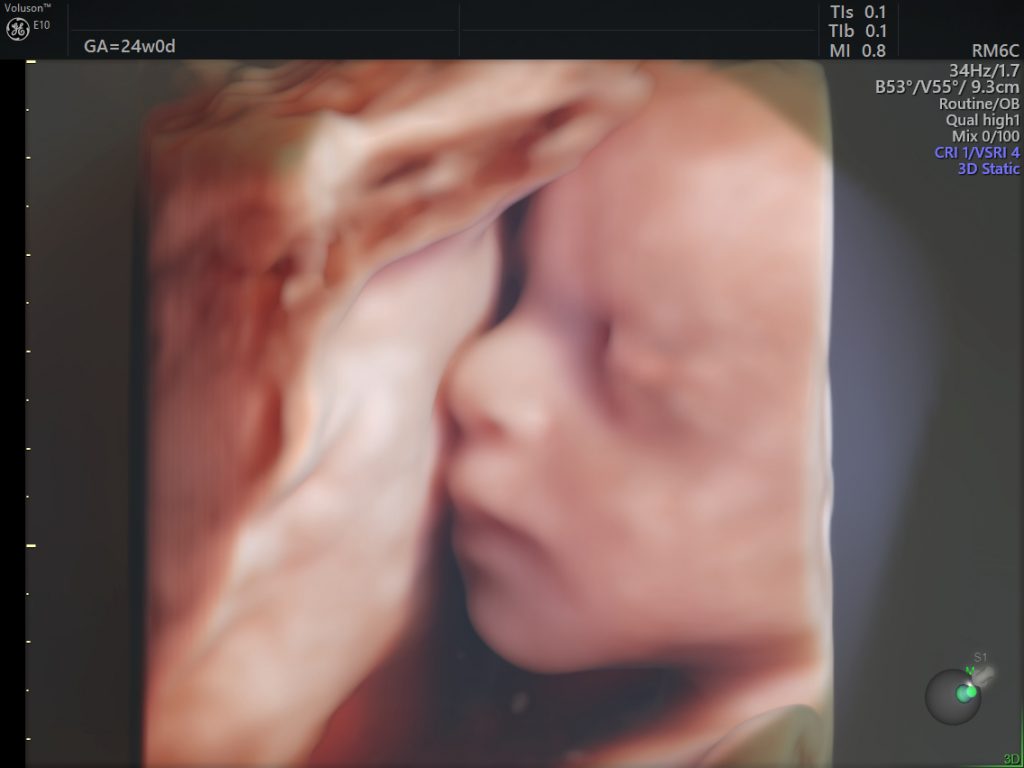

width= The fetus at 24 weeks. Image credit: GE Healthcare.